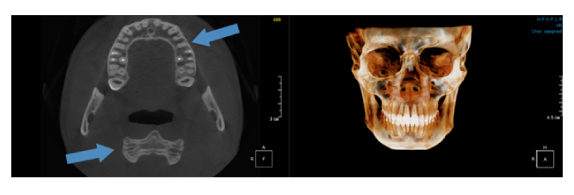

Когда мы отправляем пациента на проведение рентгенологического исследования, то подвергаем его определенному риску. Именно это нужно осознавать, так как в радиологии нет минимально безопасной дозы, поэтому любое назначение должно быть обоснованным. В связи с этим поле обзора является достаточно принципиальным параметром. Если вы врач-терапевт, занимающийся эндодонтией или ортопед, который решил оценить состояние зубов перед протезированием, то вы должны понимать, что проведение исследования с полем обзора 10x10 см будет гораздо информативнее нежели большие снимки (18x16 см и выше). В первую очередь это связано с размером вокселя, о нём я напишу чуть ниже, а второе это то, что вам придется увеличивать изображение по каждому корневому каналу, и от этого вы будете терять в качестве снимка (рис. 1). И ситуация наоборот, если вы ортодонт, то чтобы использовать весь диагностический потенциал, а также возможность загрузить данные для расчёта 3D цефалометрии, то вам нужны снимки, захватывающие весь лицевой отдел черепа. Таким образом, дентальный томограф должен обладать возможностью проведения исследований с разным FOV, обеспечивая нужды всех специалистов. Если ваша клиника базируется на терапевтическом, хирургическом и ортопедическом приёме, то на мой взгляд, можно рассмотреть дентальные томографы с полем обзора 10x10 см или 16x10 см. Последний больше актуален для тех, кто работает с ВНЧС, так как антропометрически в 16 см даже у брахицефалов сустав должен попадать. Если в клинике есть ортодонтическое направление, функциональная стоматология, ЛОР-практика или ЧЛХ, то, безусловно, вышепредставленные снимки не будут отражать всех данных, которые необходимы для диагностики и планирования лечения. Здесь лучше рассмотреть конусно-лучевые компьютерные томографы с зоной сканирования 18x16 или 20x20 см. Особо стоит отметить понятие «сшивки». Есть дентальные томографы, которые делают один цельный снимок размерами, которые описаны выше, а есть аппараты, которым нужно провести две экспозиции и сшить изображения вместе, чтобы получился необходимый объём исследования. Как правило, вторые томографы чуть дешевле, но всё зависит от того, насколько вам нужна максимальная точность исследования. Если при сшивке челюсти и зубы, как правило, совмещаются практически идеально, то на уровне позвоночного столба происходит наслоение тканей и от него уже не избавиться (рис. 2). Второй отрицательный момент – это износ оборудования, логично, что он будет быстрее, так что экономия средств — это ещё спорный вопрос.

Рис. 1. Представлены два исследования (10x10 см и 20x20 см). На обоих изображениях хорошо видна канально-корневая система зубов, но, если масштабировать второе исследование, то качество неминуемо снизится, как и диагностическая эндодонтическая эффективность.

Рис. 2. Левый снимок представлен исследованием 20x20 см единым изображением. Стрелками показаны чёткость канально-корневой системы зуба, а также позвоночника. Правый снимок представлен исследованием 16x15 см с функцией сшивки. Стрелками обозначены чёткость зуба, но двойной контур позвоночника.